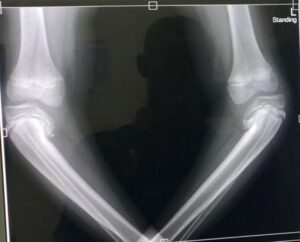

Simba Health is een Nederlandse non-profitorganisatie die sinds 1998 medisch specialistische zorg biedt en ontwikkelt voor de meest kwetsbare groepen in het merengebied van Tanzania. Ze doen dit voornamelijk in samenwerking met Missieziekenhuizen door chirurgische ingrepen, het geven van onderwijs, de aanschaf van medische apparatuur en medicijnen.